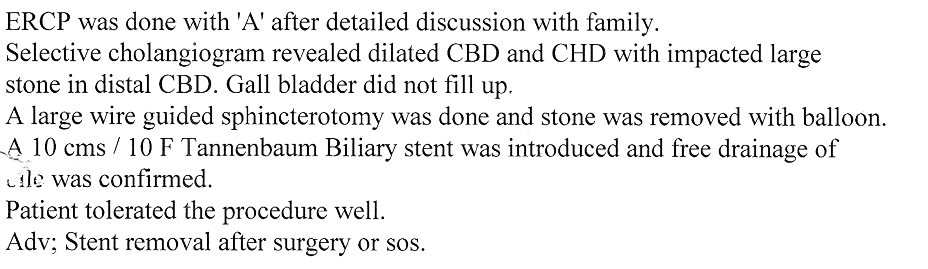

GALL BLADDER STONES TREATMENT

Endoscopic Retrograde Cholangio Pancreatography is an advanced endoscopic procedure related to

diseases of pancreas and biliary tree. Common indication for ERCP is jaundice due to obstruction

of biliary tube, which drains the bile from the liver into the intestine.

Obstruction can be due to a gallstone, which has slipped into bile tube and has blocked the bile tube.

These Stones can be removed by ERCP, without any surgery being involved.

This procedure is necessary if the patient has stones in the gallbladder and also in bile tube and

is always performed before Laparoscopic removal of gallbladder. Cancer of the gallbladder, biliary tree, pancreas,

duodenum or obstruction by lymph nodes can be responsible for jaundice and can be very effectively

treated by ERCP without any need for surgery.

This technique is important in these conditions as majority of the patients coming for jaundice are at an advanced stage of cancer and need palliative treatment to give relief from severe itching and jaundice. Infection or narrowing in the biliary tree can be treated by ERCP.

Common Biles Duct Stones

Common Biles Duct Stones

Cancer of the Bile Tube in Duodenum

Impacted Stone in Common Bile Duct

Chronic Pancreatitis is condition which can result in recurrent attacks of persistent and severe pain.

This can be due to presence of stones or narrowing of the pancreatic duct and can be treated by ERCP.

Pancreatic pseudocyst / collection of fluid is a complication of pancreatitis, which results

in abdominal pain, vomiting, fever etc. It is a serious condition which can be treated by ERCP.

Treatment of Chronic Pancreatitis by Stent

Most of the lesions of biliary system and pancreas were treated earlier by surgery with its own complications, but now with ERCP these conditions can be treated without any surgery and morbidity and mortality related to surgery, and as a cheaper option for surgery and has become treatment of choice for the same.